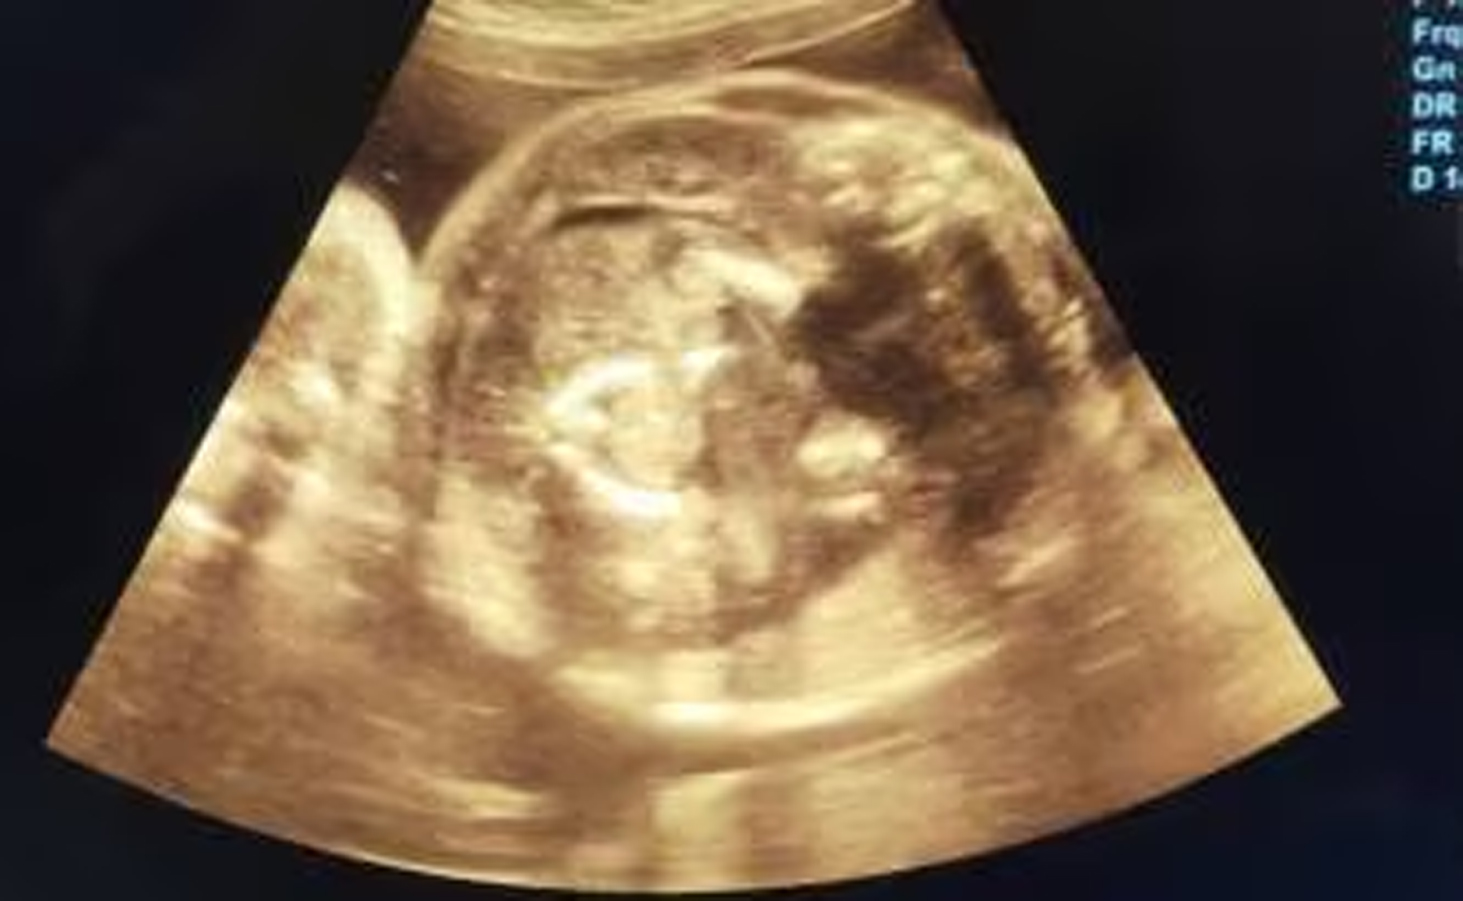

खामगाव- बुलढाणा जिल्हा सामान्य रुग्णालयात तपासणी करण्यासाठी आलेल्या गर्भवती महिलेची सोनोग्राफी केल्यानंतर तिच्या पोटातील बाळाच्या पोटात बाळ असल्याचा धक्कादायक प्रकार समोर आला आहे. या महिलेचं वय 32 वर्ष असून तिला याआधी दोन अपत्यं आहेत. हे एक अत्यंत दुर्मीळ प्रकरण असून या गर्भधारणेला मेडिकल भाषेत ’फिटस इन फिटू’ असे म्हणतात.

साधारणपणे 5 लाख गर्भवती महिलांमध्ये अशी एखादी केस आढळत्ो. जगात अशी घटना 1983 मध्ये पहिल्यांदा नोंदवली गेली. त्यानंतर आतापर्यंत जागतिक स्तरावर सुद्धा 200 पेक्षा कमी केसेस अर्भकामध्ये अर्भक असल्याच्या घडल्या आहेत. सदर महिलेला प्रसुतीसाठी संभाजीनगरला पाठविले आहे ही महिला घाटाखालील रहिवासी असून नियमित नऊ तपासणीसाठी बुलढाणा जिल्हा सामान्य रुग्णालयात आली होती. दरम्यान स्त्रीरोग तज्ञ डॉ.प्रसाद अग्रवाल यांनी सदर महिलेची सोनोग्राफी करताना भुवया उंचावल्या, त्यांनी परत परत तपासणी केली आणि मग त्यांना कळून चुकले की, आईच्या पोटात बाळ आहेच पण बाळाच्या पोटातही बाळ आहे. त्यांनी तातडीने ही बाब जिल्हा शल्यचिकित्सक डॉ. भागवत भुसारी, शासकीय वैद्यकीय महाविद्यालयाचे अधिष्ठाता डॉ. झिने व स्त्री रुग्णालयाचे वैद्यकीय अधीक्षक डॉ. पाटील यांच्या कानावर टाकली. सदर वरिष्ठांच्या मार्गदर्शनात पुन्हा सोनोग्राफी करण्यात आली. बाळाच्या पोटात बाळ स्पष्टपणे दिसत होत्ो. कुठलाही धोका न पत्करता सदर महिलेची प्रसुती सुलभ होण्याकरीता आणि पोटातील बाळ वाचावे यासाठी तिला छत्रपती संभाजी नगर या ठिकाणी हलविण्यात आले आहे.